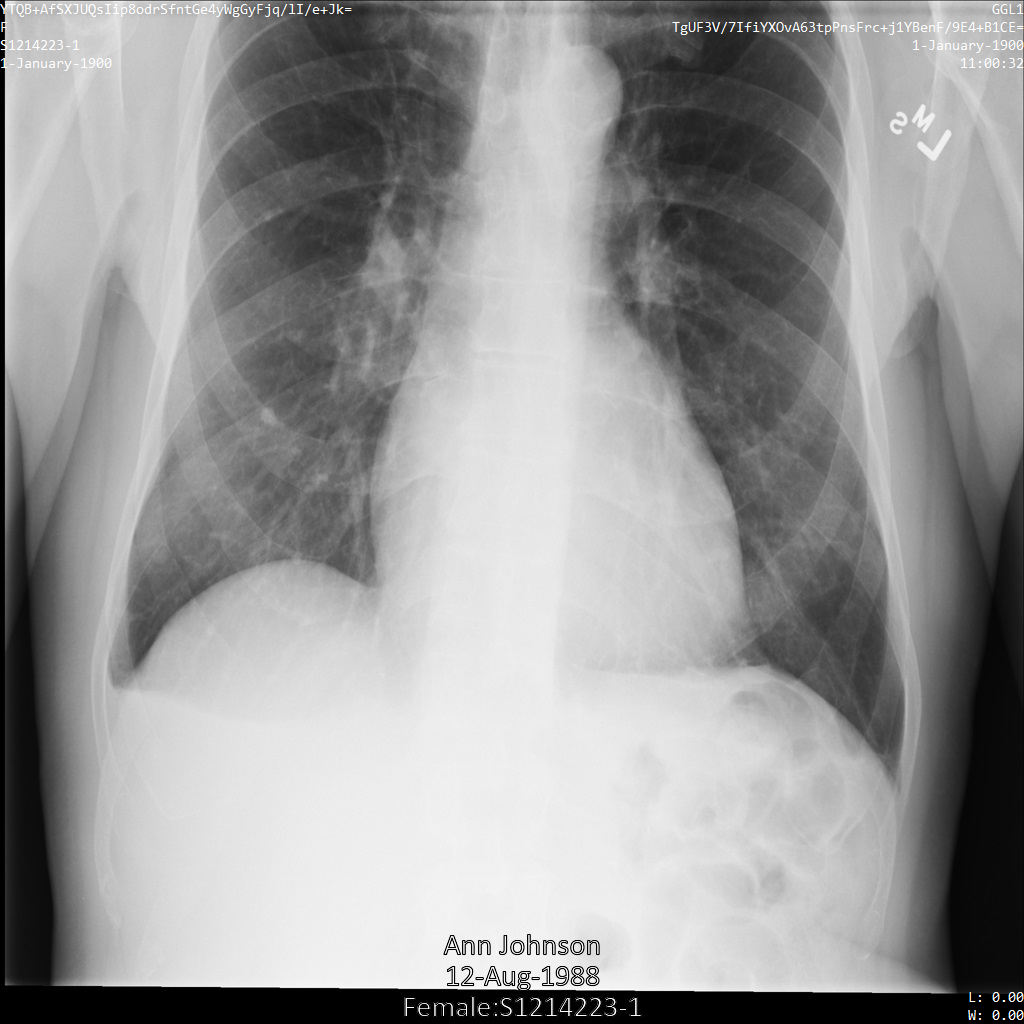

A imagem seguinte mostra uma radiografia não ocultada de um paciente:

Depois de enviar a imagem para a Cloud Healthcare API através da opção REDACT_SENSITIVE_TEXT, a imagem é apresentada da seguinte forma:

Pode ver que ocorreu o seguinte:

- O

PERSON_NAMEna parte inferior esquerda da imagem foi ocultado - O

DATEna parte inferior esquerda da imagem foi ocultado

O sexo do paciente não foi ocultado porque não é considerado texto sensível de acordo com os infoTypes DICOM predefinidos.